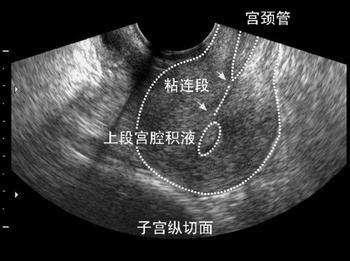

异常结果: (1) 阴道检查:检查宫颈的位置、外口大小、形状以及分泌物量、性状有无宫颈糜烂等,同时用细菌学检查宫颈管粘液,必要的时候还要做刮片或者阴道镜检。 (2) 探针检查:探测宫颈管的行径方向、长度以及它与宫颈的比列是否存在异常、粘连、狭窄等等。对有异常可疑患者,应该进一步做造影检查。 (3) 造影检查:子宫和输卵管的病变都能够通过造影检查发现,而且造影检查还可以对研究不孕症产生有利的效果。对于颈管内赘生物,先天性畸形狭窄、粘连以及子宫屈曲都能够明确诊断。 需要检查的人群:外阴瘙痒、或灼热不适,下腹部或腰骶部疼痛,每于性交、经期和排便时加重。也有自觉双下肢无力,口苦,恶心,小便发黄等症状的人群。

无菌长棉签取后穹窿部白带少许,放在盛有1-2滴生理盐水的玻片上,立即在显微镜下进行镜检。 采用膨宫介质扩张宫腔,通过纤维导光束和透镜将冷光源经宫腔镜导入宫腔内,直视下观察宫颈管、宫颈内口、宫内膜及输卵管开口,以便针对病变组织直观准确取材并送病理检查。 通过导管向宫腔及输卵管注入造影剂,行X线透视及摄片,根据造影剂在输卵管及盆腔内的显影情况了解输卵管是否通畅、阻塞部位及宫腔形态。